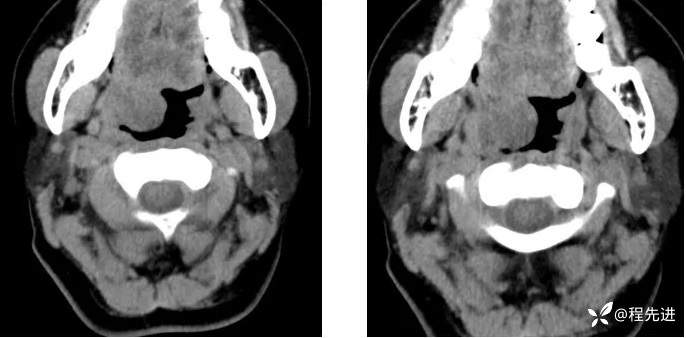

CT平扫: